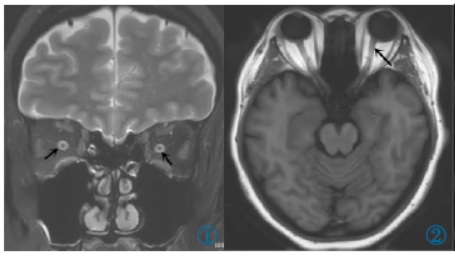

图1冠状面T2WI示双侧视神经鞘扩张。图2横断面T1WI示眼球后部变平,左侧视神经走形扭曲。

眼球后壁巩膜变扁平多由视乳头水肿导致,在排除视神经炎、缺血性视神经病及视神经肿瘤等病因后多可认为是由IIH引起的,是诊断IIH特异性非常高的影像学征象。视神经走行迂曲是因为眼外肌和韧带等结构的固定作用,使视神经周围增高的脑脊液压力传导至视神经前端的球茎联合部时改变眼球后壁和视神经的形状来缓解压力的增高而造成的。

IIH患者静脉窦狭窄发生率较高,有学者认为颅内压的增高压迫静脉窦,引起静脉窦顺应性减低,从而出现窦壁凹陷而使静脉窦狭窄,增强MRI容积扫描联合MRV对颅内静脉窦病变具有良好的诊断价值。视神经鞘扩张的发生率仅次于空蝶鞍,跟其他IIH影像学表现相比,其诊断意义更大。视神经鞘扩张和颅内静脉窦狭窄诊断IIH有较高的敏感性和特异性。